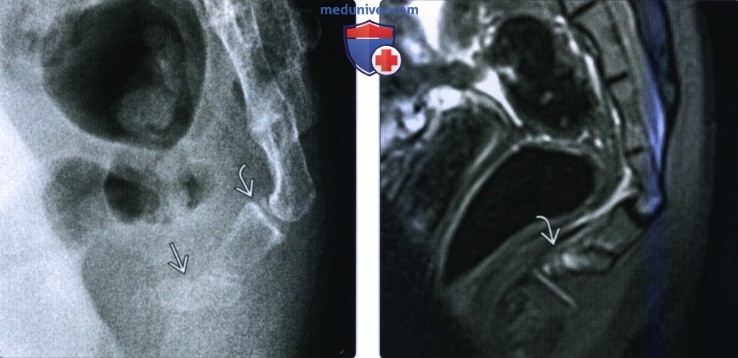

Рентгеновские снимки крестцово-копчикового отдела позвоночника